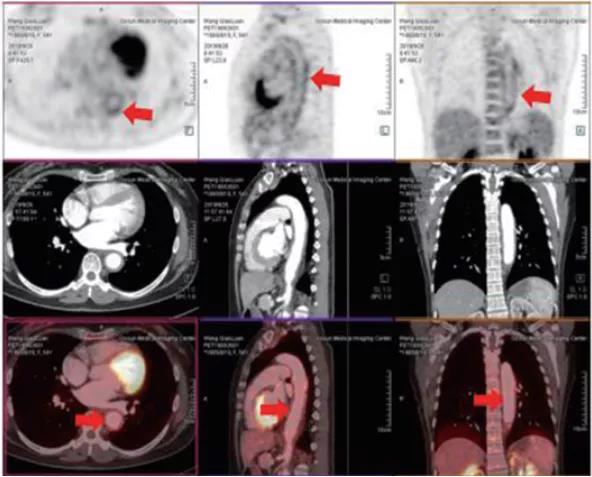

一、腫瘤疾病的應用

1、腫瘤的早期診斷和鑒別診斷

2、對惡性腫瘤進行更準確分期,全面了解全身病變情況

3、已發(fā)現(xiàn)腫瘤轉移者,尋找原發(fā)灶

4、腫瘤標志物升高或副腫瘤綜合征患者,尋找腫瘤病灶所在

5、腫瘤治療后效果評估

6、腫瘤復發(fā)的監(jiān)測

二、非腫瘤顯像

1、癲癇患者癇灶定位2、風濕免疫性疾病患者明確感染病變的部位、范圍及活動程度,并評估療效3、早期診斷,并能準確評估大血管炎的活動情況三、PET/CT-MR的PET/MR融合技術應用四、PET/CT-MR特色診斷技術

?精準:本設備是新一代PET/CT,圖像重建矩陣可達400×400,其分辨率達到毫米;其FlowMotion掃描技術提供極精細器官細節(jié)顯示,并對病灶提供精確的可重復定量分析;顯著提高了微小病灶的檢出和確診率。

?全 面:PET/CT是通過血管內注射示蹤劑,采用動態(tài)連續(xù)掃描全身,動態(tài)數(shù)據(jù)分析,跟蹤檢查精準定位,全身病變無處遁形。?快 速:本設備采用流式掃描技術,在3-5分鐘可以完成高質量的全身掃描,具有掃描速度快、靈敏度高的特點,可快速檢查全身,提高舒適度和診斷效率。